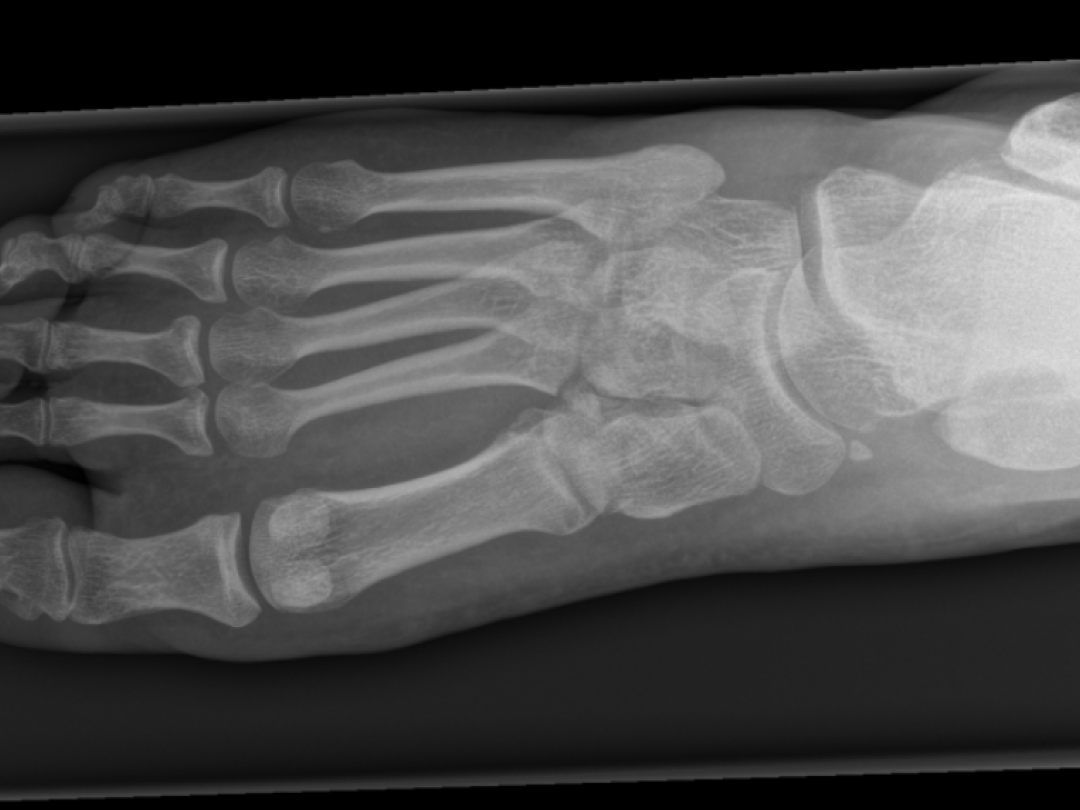

Het gewricht van Lisfranc is het gewricht tussen de middenvoet en de voorvoet (figuur 1). Circa 0,2% van alle fracturen betreft een letsel van dit gewricht. Het zogenoemde Lisfranc-letsel heeft een incidentie van 1 op de 55.000 mensen per jaar.1 Door de complexiteit van het gewricht, de subtiliteit van het letsel, de verschillen in de gebruikte beeldvormingstechnieken en een gebrek aan kennis bij de behandelaar, wordt 20-50% van deze letsels initieel gemist.2 Wanneer de diagnose te laat wordt gesteld, kan de behandeling tekortschieten, met een slechte prognose tot gevolg. Om die reden is het van groot belang dat artsen dit letsel kennen en weten met welke onderzoeken de diagnose het best gesteld kan worden.

Anatomie van het Lisfranc-gewricht

Figuur 1 | Anatomie van het Lisfranc-gewricht

Het Lisfranc-gewricht is het gewricht tussen de basis van metatarsalia (MT-)I-V en het os cuneiforme mediale (C1), os cuneiforme intermedium (C2) en os cuneiforme laterale (C3) en het os cuboideum. Het gewricht kan worden opgedeeld in drie functionele pijlers: mediaal, centraal en lateraal. Het heeft ossale stabiliteit doordat de basis van MT-I tot en met -V in het frontale vlak samen een ‘romeinse boog’ vormen (dwarsgewelf), waarbij de basis van MT-II dient als hoeksteen. Verder ontleent het gewricht stabiliteit aan de sterke ligamenten die de tarsometatarsale, intermetatarsale en intercuneiforme gewrichten overspannen, waarvan de plantair gelegen ligamenten de sterkste verbindingen vormen. Hoewel er ligamentaire verbindingen lopen tussen de basis van MT-II tot en met -V, ontbreekt deze verbinding tussen basis van MT-I en -II. Het Lisfranc-ligament, dat een sterke verbinding vormt tussen os cuneiforme mediale en de basis van MT-II – plantair ook met de basis van MT-III –, is een van de belangrijkste stabilisatoren van de middenvoet. Letsel van dit ligament leidt veelal tot instabiliteit tussen de mediale en centrale pijler. Dit kan leiden tot deformiteit wanneer het dwarsgewelf van de voet inzakt.